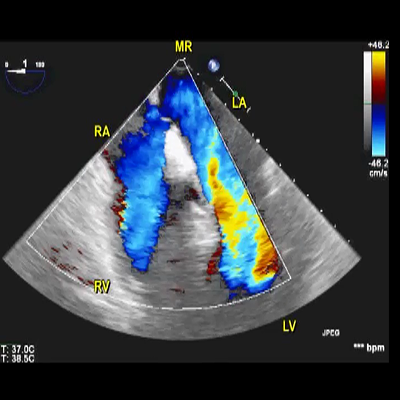

Transthoracic 2D echocardiography apical 4-chamber view

Transthoracic 2D echocardiography appendicular view

Transesophageal echocardiography mid-esophageal view

Transthoracic echocardiography off-axis view

Transthoracic echocardiography apical 4-chamber view